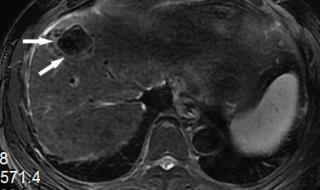

原发性肝癌